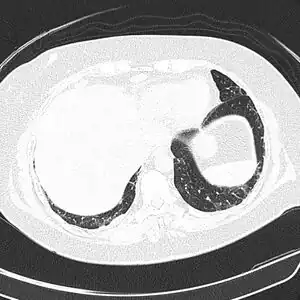

CT scan lungs: mass in right upper lobe

FDG PET/CT - Multiple nodules (some cavitating) in the left lower lobe